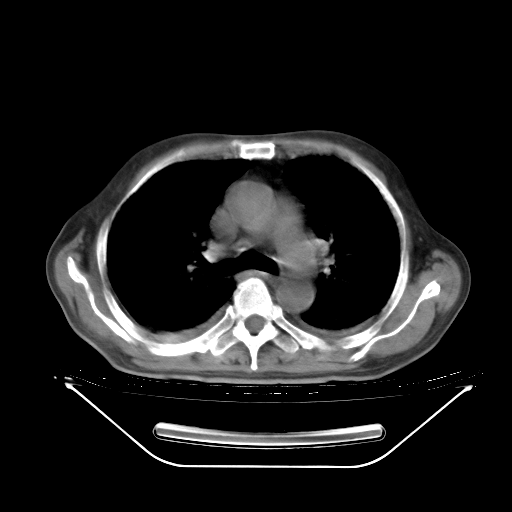

胸腹部CT,诊断意见:左上肺叶钙化灶、左侧胸膜局限性增厚并钙化、胆囊炎。描述部分肺组织呈磨玻璃样改变。